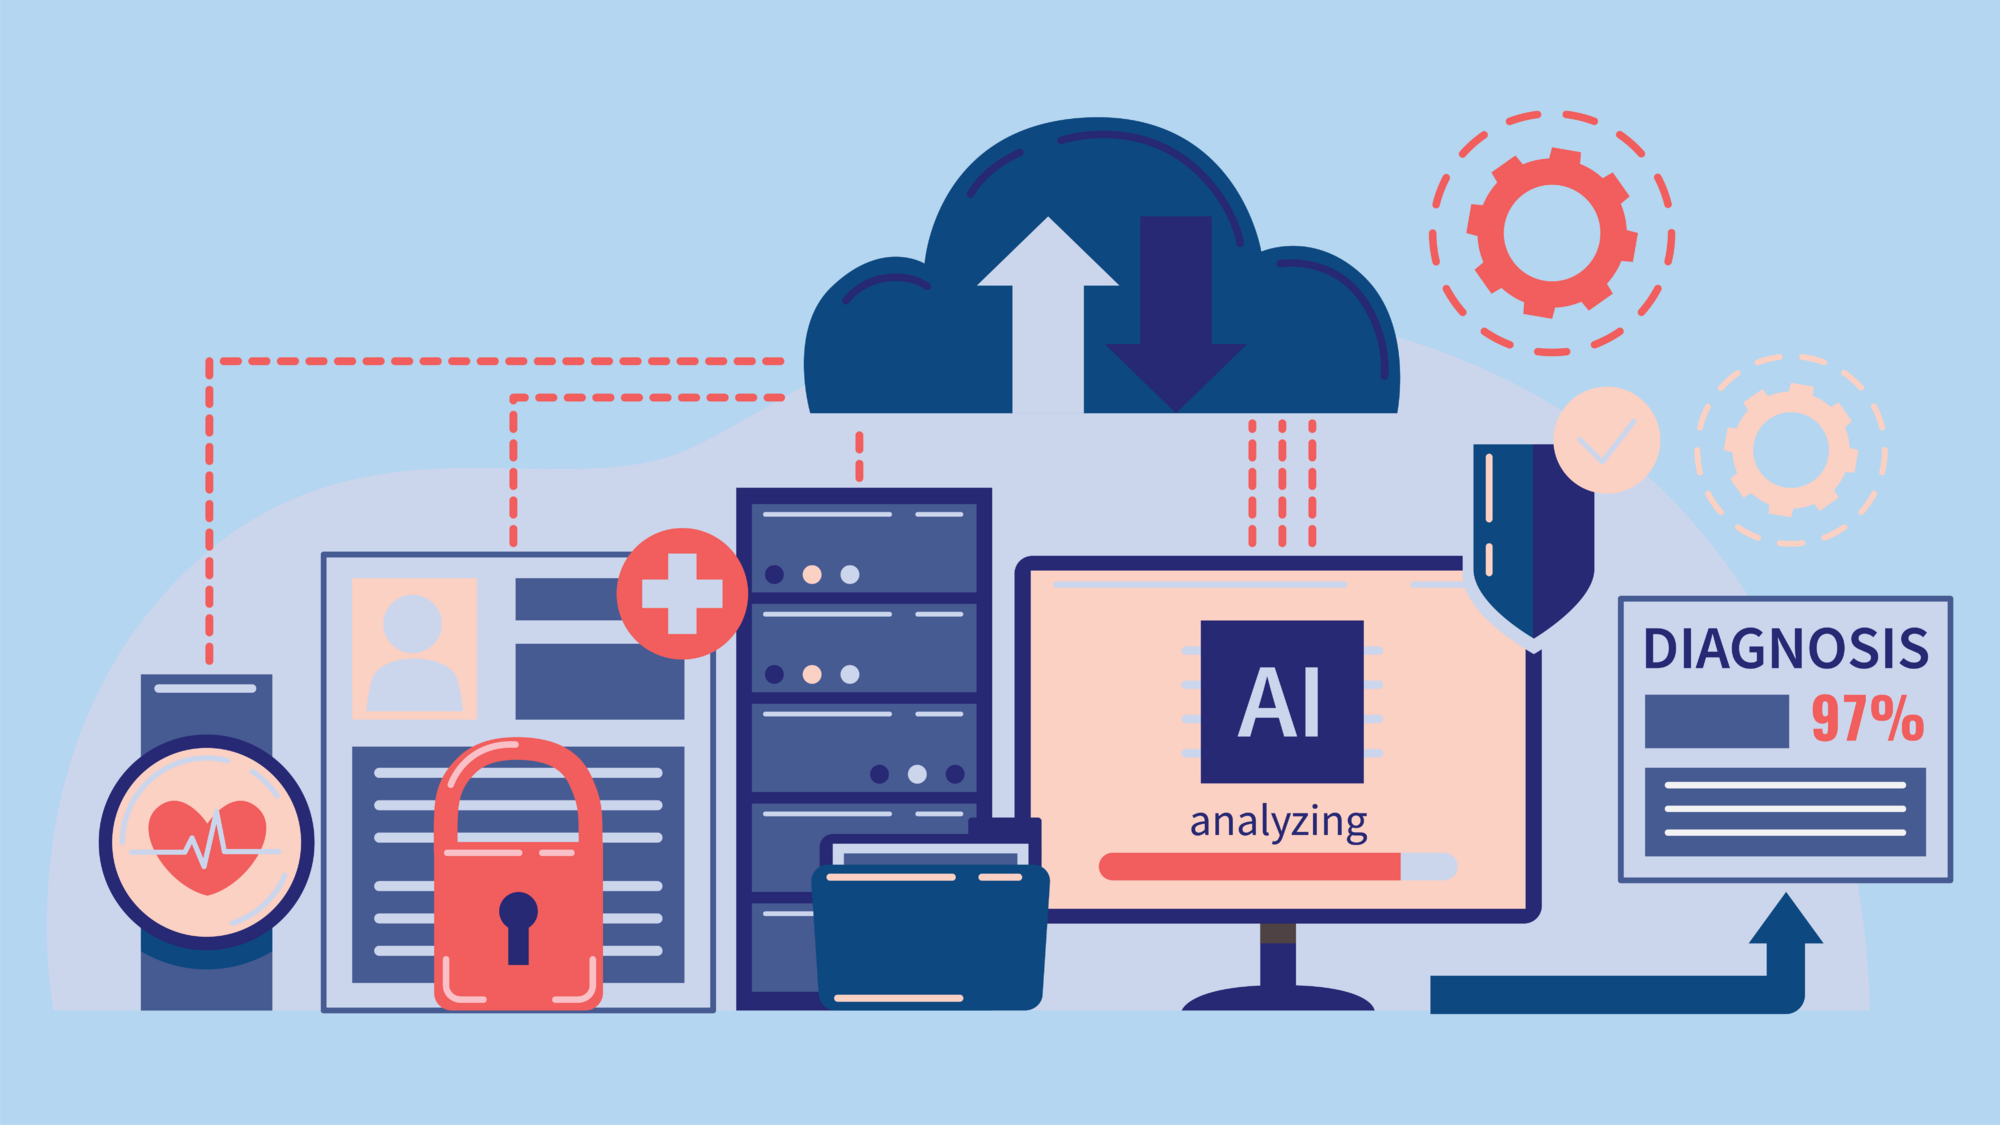

The Sensor-S study demonstrates how data from sensors, wearables, continuous glucose monitors (CGMs), and patient-reported outcome measures (PROMs) can be integrated within a scalable digital research infrastructure. The result is a blueprint for data-driven, patient-centered rehabilitation—developed using D4L Collect.